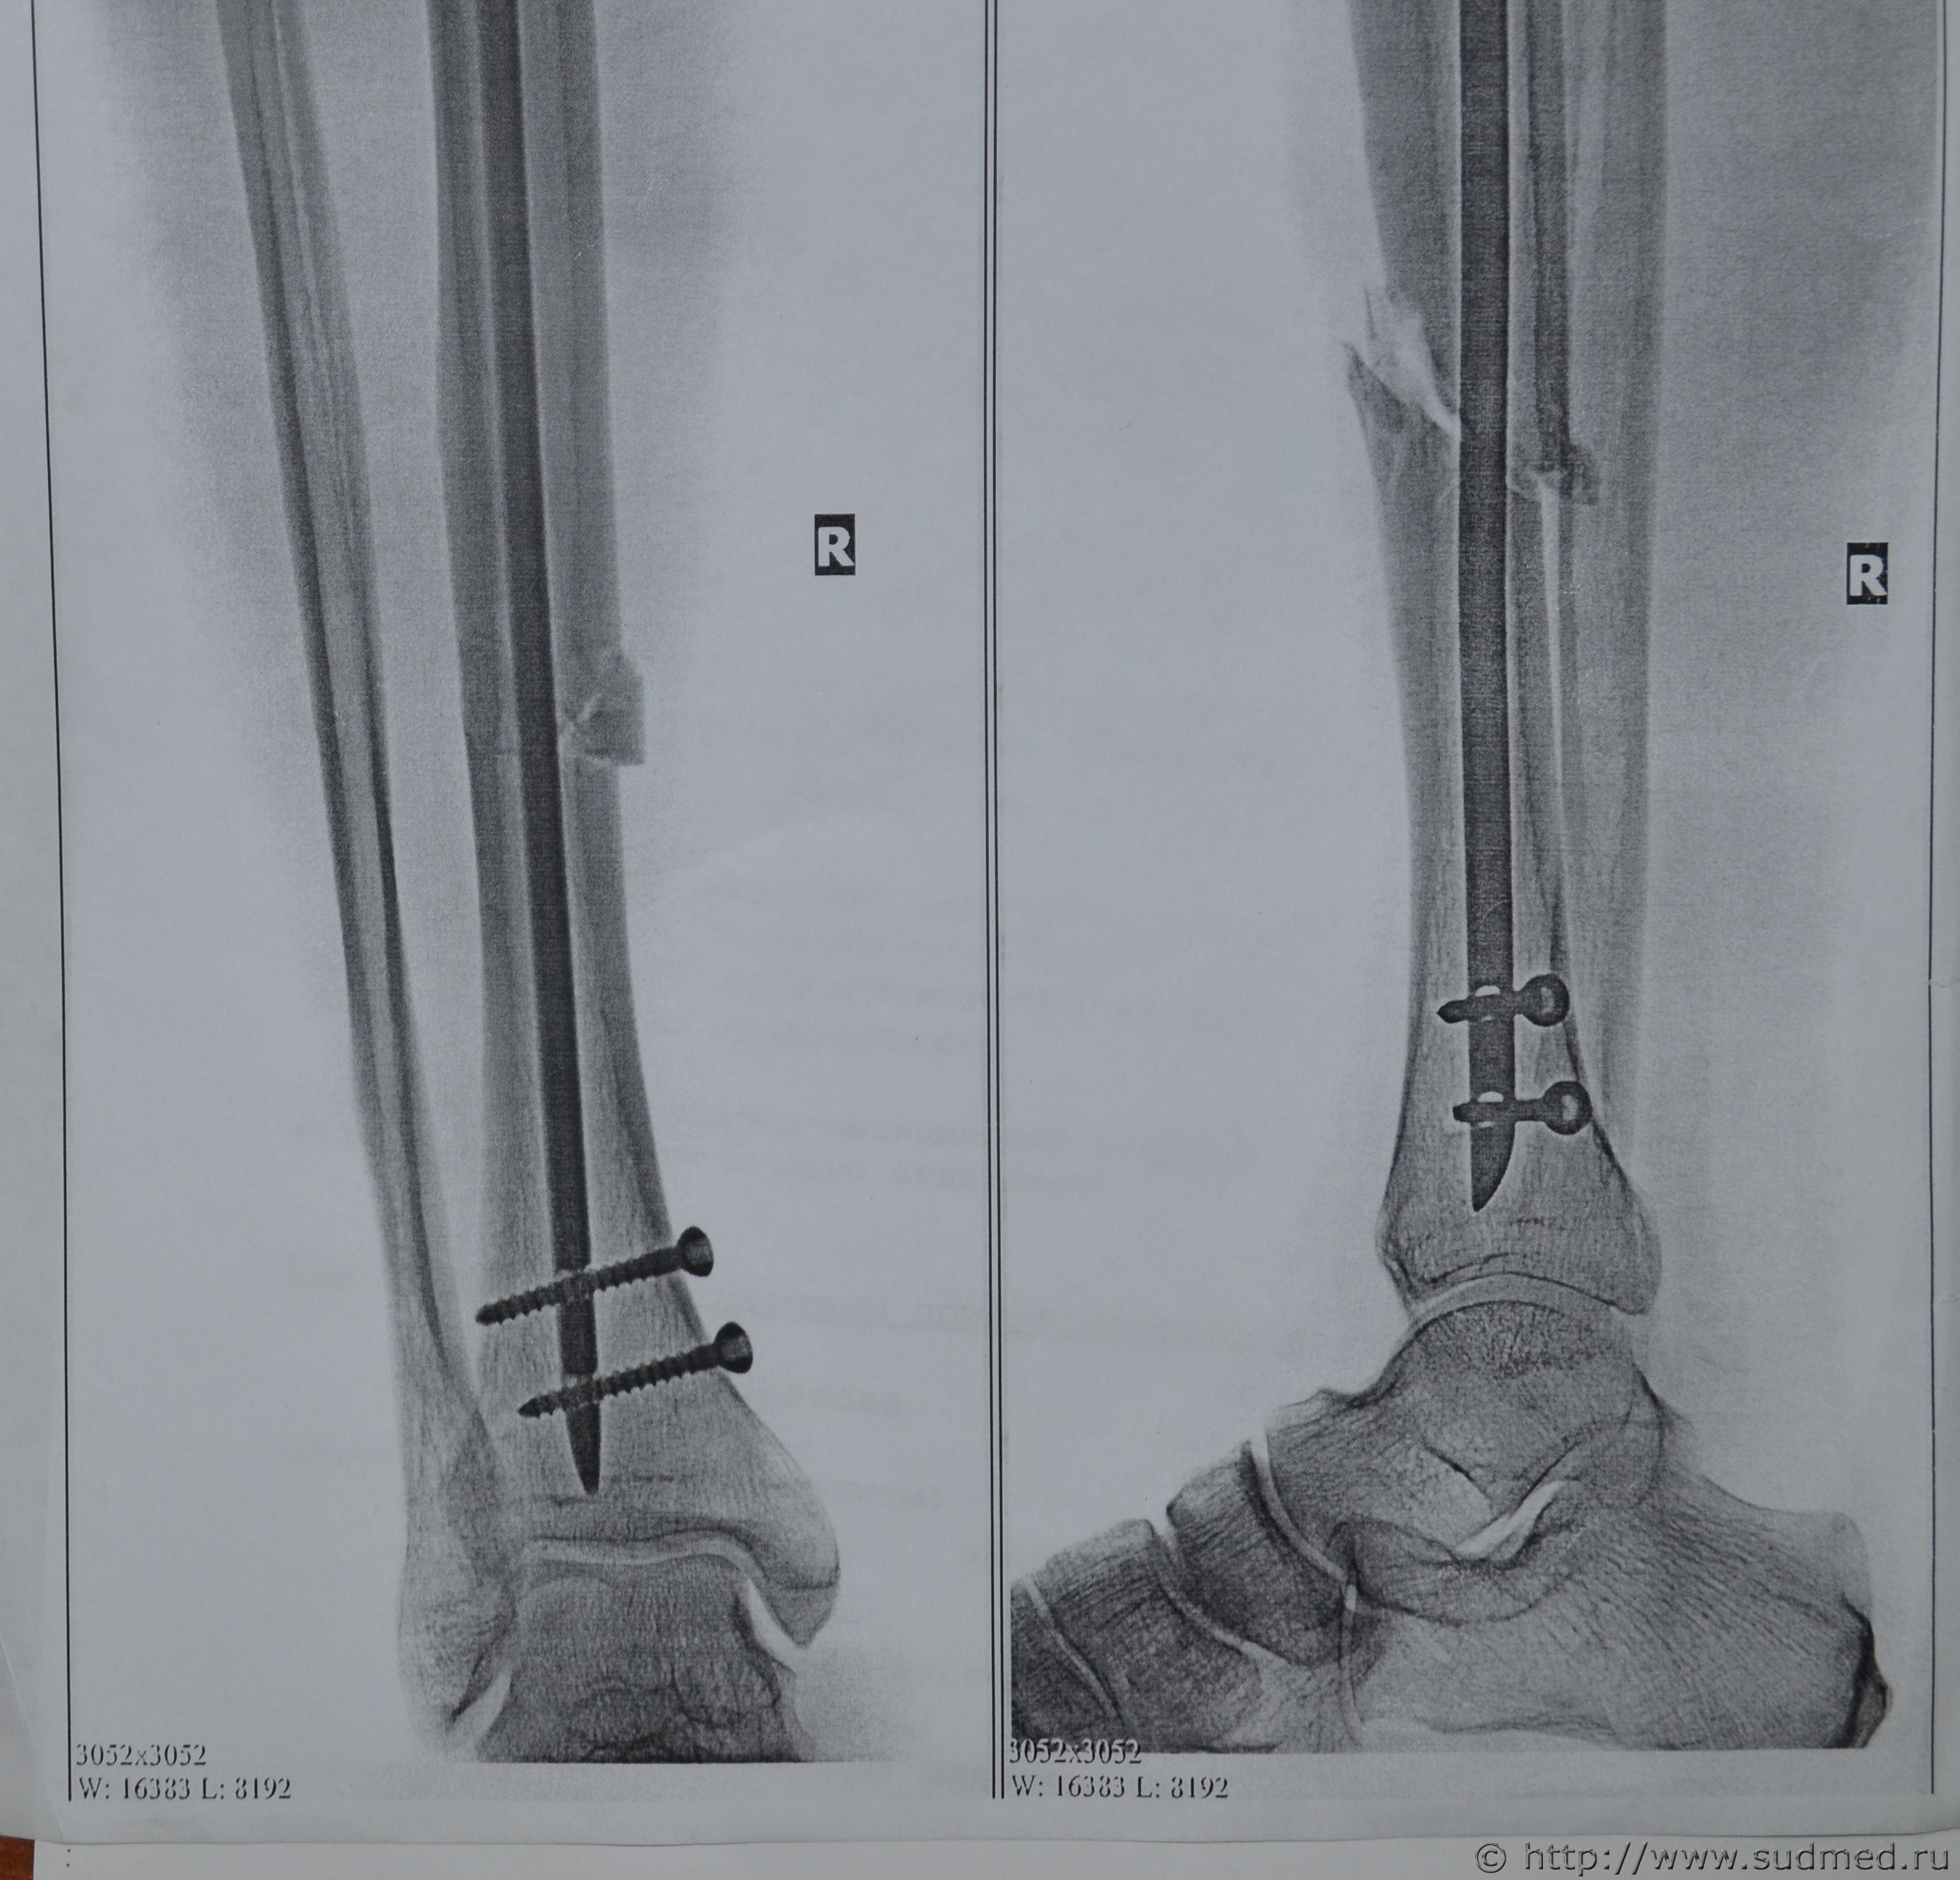

Со слов потерпевшего 1980г.р. ему наносят удар ногой в область медиальной поверхности средней трети правой голени, когда он располагался в положении стоя. На рентгенограмме определяется перелом большеберцовой кости клиновидной формы, основанием обращенный в сторону внутренней поверхности голени (снимок могу приложить при необходимости) . Жулик утверждает, что потерпевший нанес ему удар правой голенью по его голени вследствие чего у потерпевшего и образовался прелом (точка приложения совпадает и у жулика и у потерпевшего). Из вышесказанного вытекает ряд вопросов:

Предоставляю снимок

Нашел снимок целиком. У подозреваемого кровоподтек на голени. Потерпевший демонстрирует удар подозреваемым по его голени; подозреваемый - что потерпевший сам его ударил своей голенью. Точка приложения совпадает по двум версиям. Можно ли в данном случае продифференцировать: был ли это удар предметом, или удар о предмет?

Снимок конечно не идеален, после ИМОС, видимо выполнен на бумажном носителе?!

Образование такого перелома в результате непрямой травмы исключено (смотри т.1 "Диагностикум" Крюкова В.Н.), после прямого удара в среднюю треть голени с образованием треугольника Мессерера, подворот ноги привел бы возможно, как вариант, к переломам лодыжек или винтообразному перелому м/берцовой кости.

Ну а где же тогда следствие деформации изгиба на малоберцовой кости, очень это маловероятно! В этом случае обе кости ломаются. Остается вариант только локального воздействия тупого твердого предмета. В случае удара о подобный по твердости предмет повреждений может не случится ЛИБО неминуемы повреждения ОБЕИХ СОУДАРЯЕМЫХ поверхностей, значит, более вероятен вариант торавмирования по версии потерпевшего